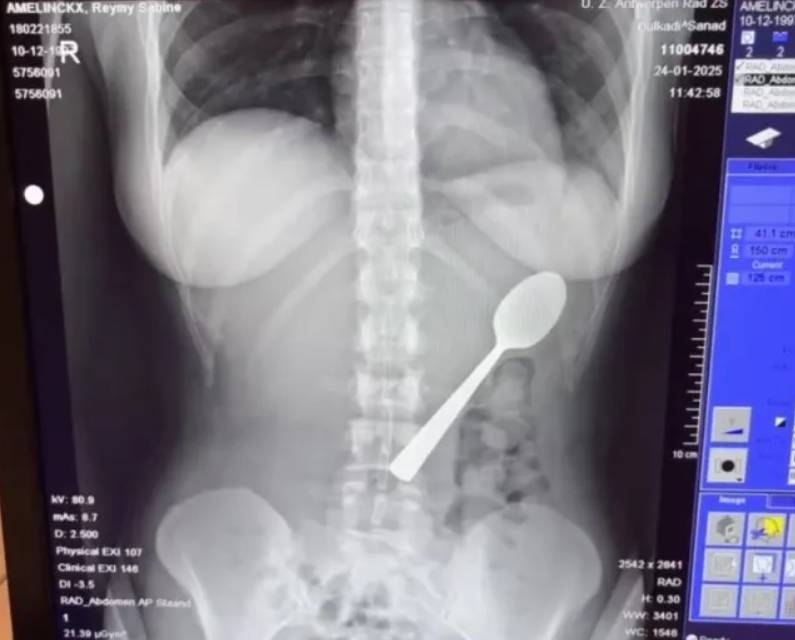

Một phụ nữ Bỉ vô tình nuốt trọn chiếc thìa dài 17 cm sau khi chó cưng bất ngờ nhảy lên người lúc cô đang ăn sữa chua.

Reymy Amelinckx, 28 tuổi, cho biết sự cố xảy ra hôm 24/1, khi cô đang ngồi ăn sữa chua trên ghế sofa thì chú chó cưng Marley, giống Hungarian Vizsla, bất ngờ nhảy lên lòng.

Sau khi được đưa ngay tới bệnh viện, các bác sĩ nói chiếc thìa quá lớn nên không thể tự đào thải qua đường tiêu hóa, buộc cô phải về nhà chờ đến khi được sắp xếp nội soi dạ dày.

Hai ngày sau, thìa được lấy ra bằng gây tê tại chỗ. Trong quá trình thực hiện, các bác sĩ phải xoay chiếc thìa trong dạ dày, khiến cô bị xuất huyết nhẹ ở niêm mạc dạ dày.